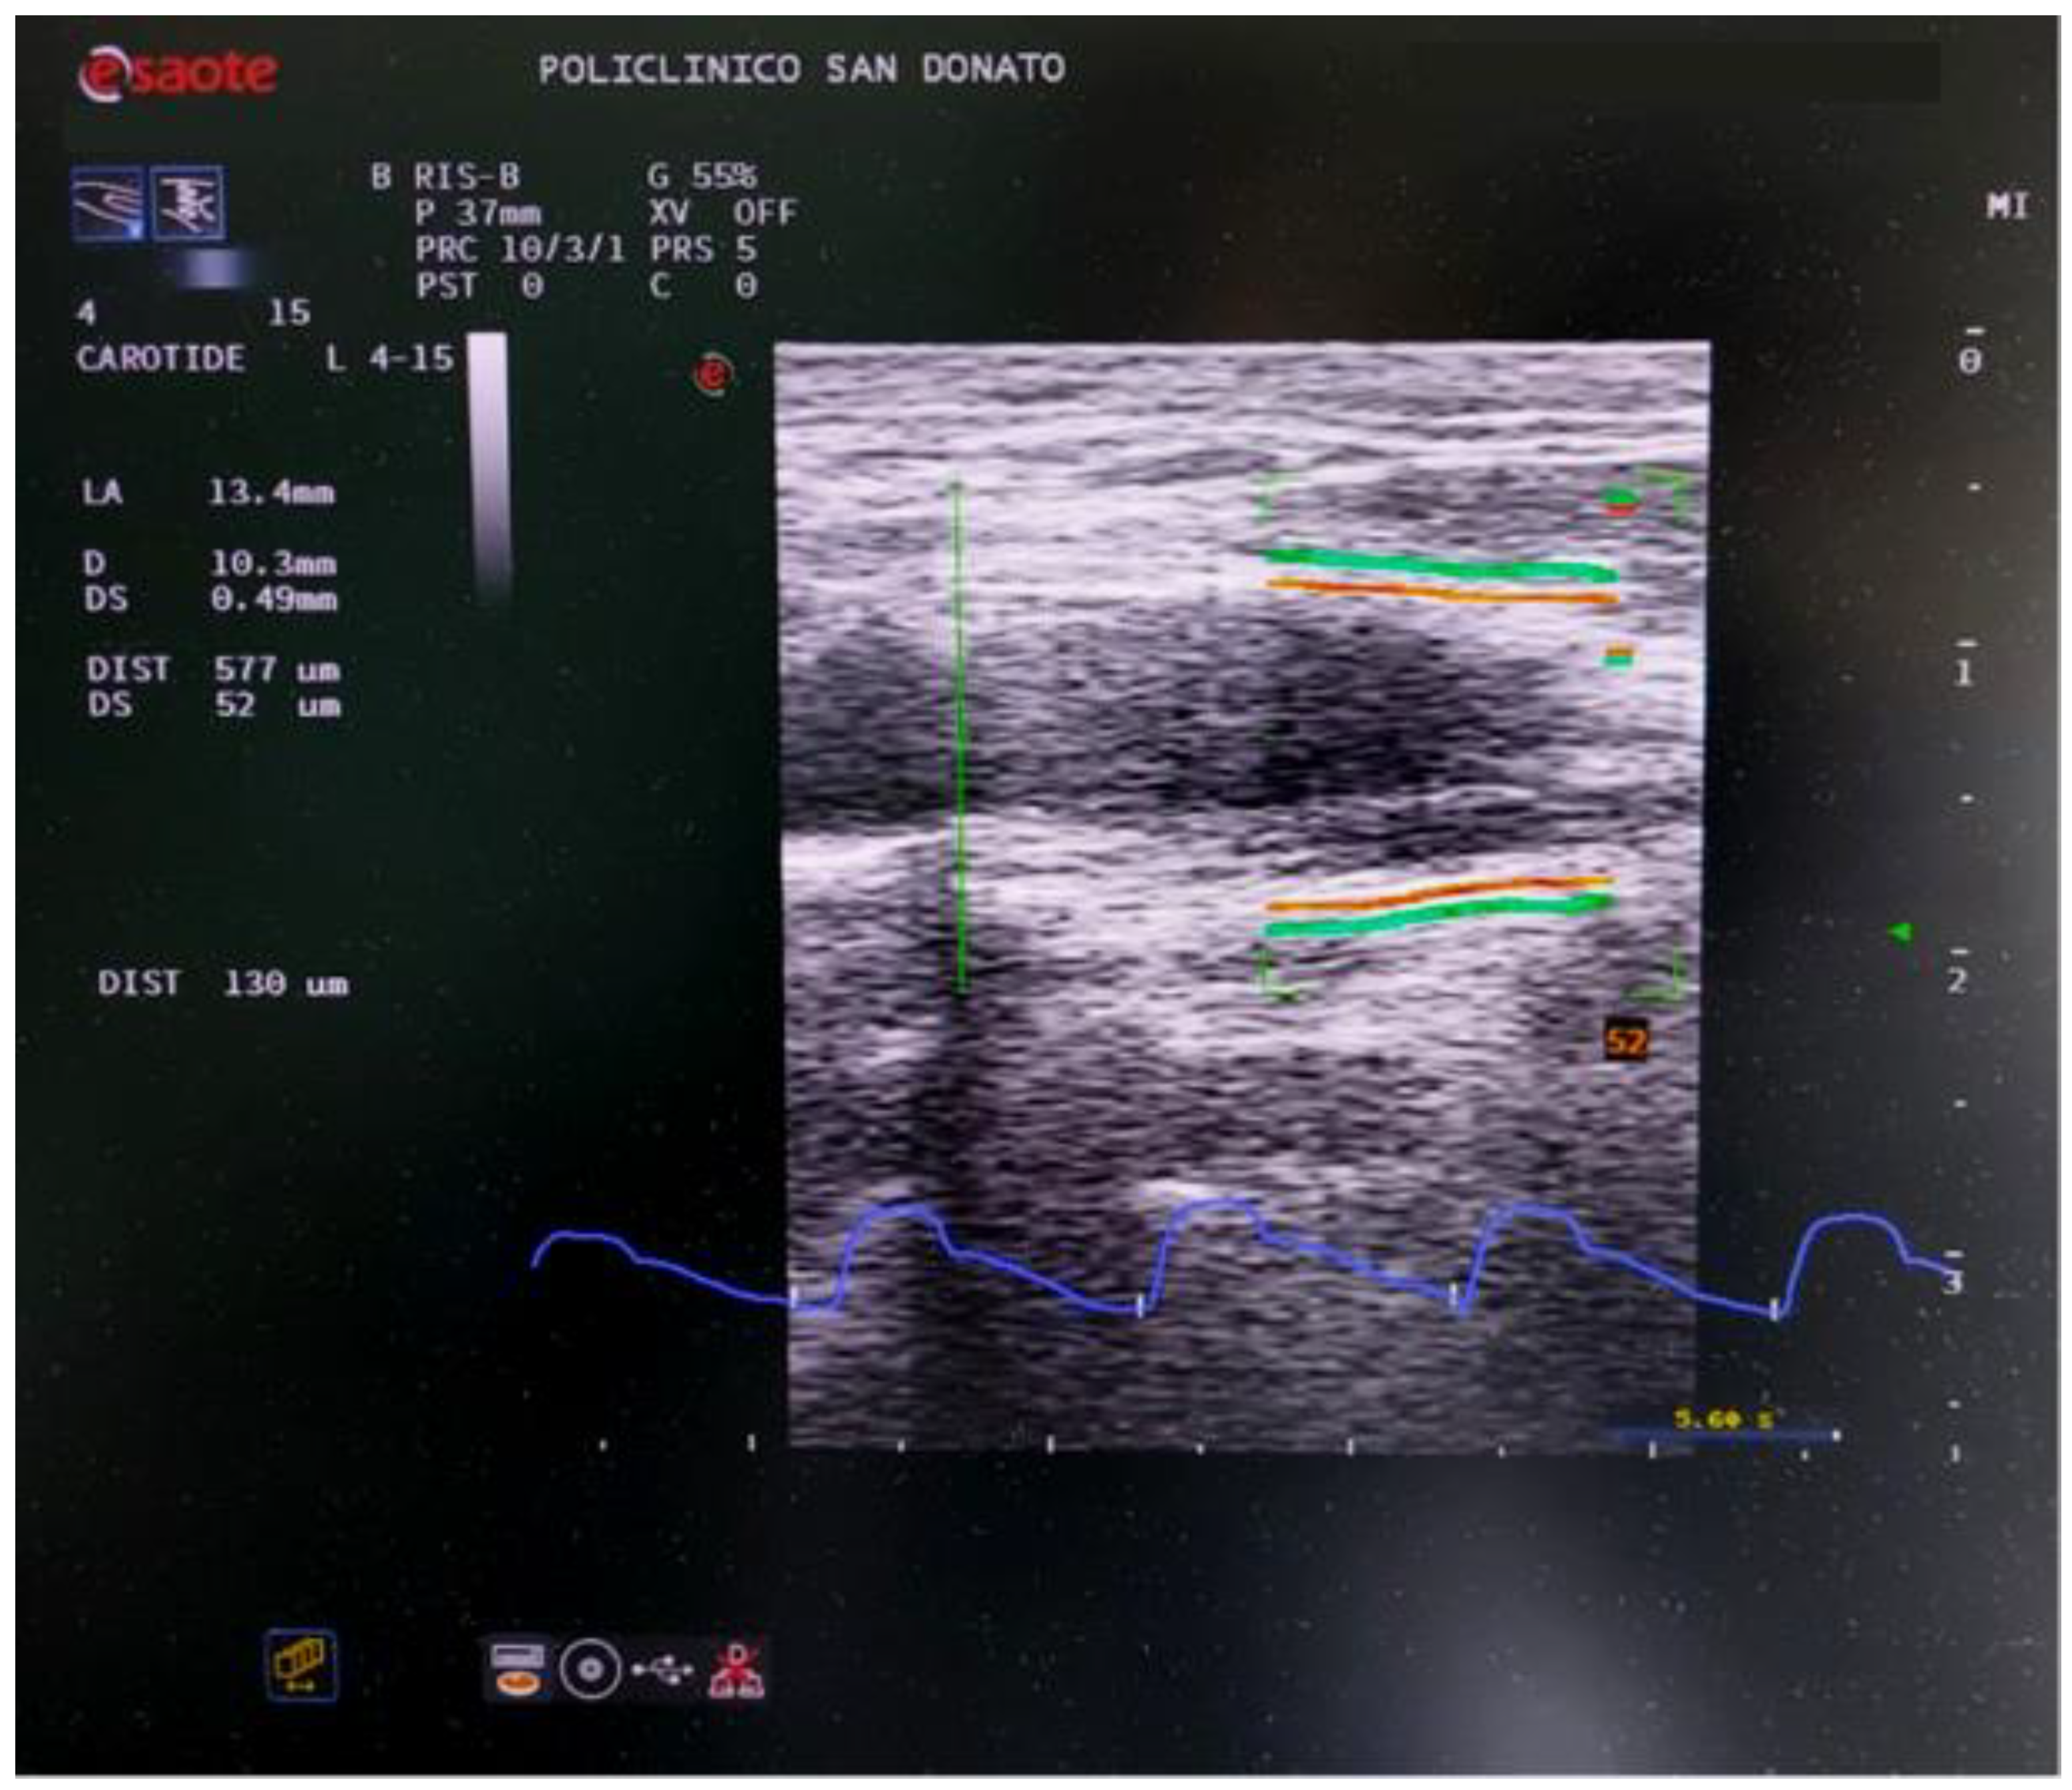

The QAS was performed with the patient in a supine position and with a slight neck extension, on the side of the carotid stenosis. The linear probe was placed along a longitudinal axis on the distal part of the common carotid artery just below the origin of the atherosclerotic plaque, at least 10 mm far from the origin of the bulb, strictly perpendicular to the ultrasound beam, with both walls clearly visualized (Figure 1). Then, the QAS algorithm was run, with automatic real-time measurement of the change in diameter of the vessel walls between the systolic and diastolic phases, caused by the traveling blood pressure wave originating by heart pumping (Figure 2). The local carotid pressure waveform is derived from brachial pressure values and vessel cross-sectional areas during the cardiac cycles [14]. All the measures are automatically calculated by the system starting from distension and pressure waveforms and provided in a report (Figure 3) [15].

Figure 2.

Screenshot of the QAS evaluation of the carotid artery on the diseased side. The red lines represent the vessel wall average diameter tracking. The green lines are associated with the wall distension. The real distensibility represented by the green line movement is “amplified” giving a fast estimation of the vessel’s elastic properties. The velocity curve over time is shown in blue below the ultrasound image.